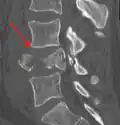

A burst fracture is a type of traumatic spinal injury in which a vertebra breaks from a high-energy axial load (e.g., traffic collisions or falls from a great height or high speed, and some kinds of seizures), with shards of vertebra penetrating surrounding tissues and sometimes the spinal canal.[1] The burst fracture is categorized by the "severity of the deformity, the severity of (spinal) canal compromise, the degree of loss of vertebral body height, and the degree of neurologic deficit."[2] Burst fractures are considered more severe than compression fractures because long-term neurological damage can follow. The neurologic deficits can reach their full extent immediately, or can progress for a prolonged time.

Diagnosis is by medical imaging.